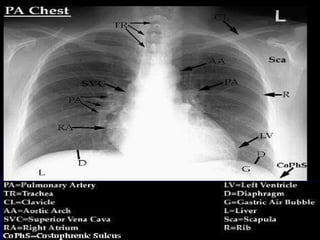

NORMAL CHEST X-RAY PA LATERAL Two (2) projections are needed for most x-rays to locate structures in 3 planes  (1)Right or Left , (2) Anterior or Posterior)  or (3) Superior or Inferior.

AORTIC ARCH LT. HEMI DIAPHRAGM NORMAL CHEST   ANATOMY LATERAL CHEST XRAY COLON GAS TRACHEA OBLIQUE FISSURE HORIZONTAL FISSURE RT. HEMI DIAPHRAGM Diaphragm-AP view Diaphragm- Lateral view LT. LT. RT. LT.